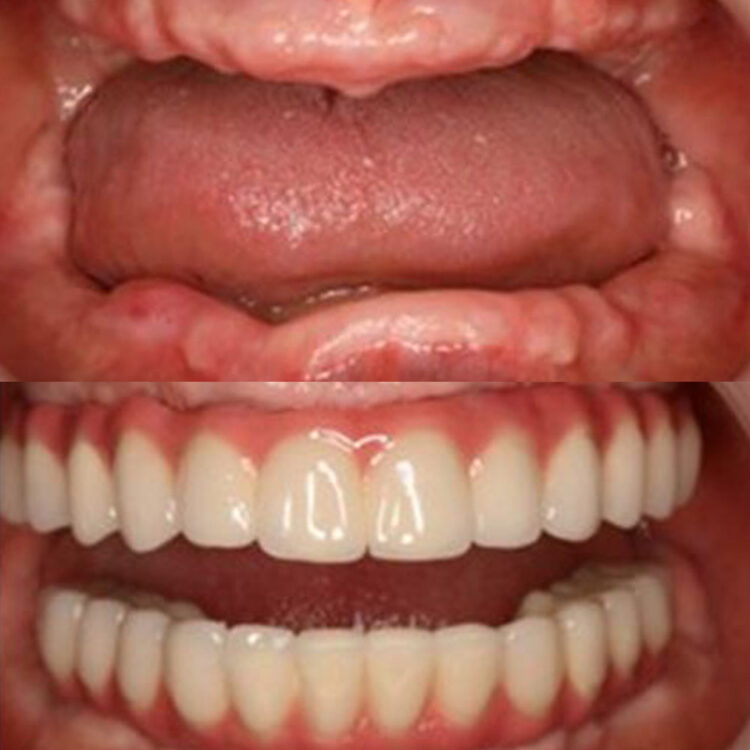

The “All-On-4 ™” dental implant treatment involves the fixing of acrylic veneers onto a prosthesis, which, in turn is attached to dental implants to ensure a perfect cosmetic result. The acrylic veneers used are extremely robust, and unlike a normal prosthesis, will blend the gingival colour seamlessly with the patient’s own palate, providing a flawless and comfortable fit. After the two-day treatment has been completed the patient will be able to return to their usual social life bearing a wonderfully perfect smile.

- The final result will offer comfort, and the aesthetically designed result will increase the patient’s quality of life.